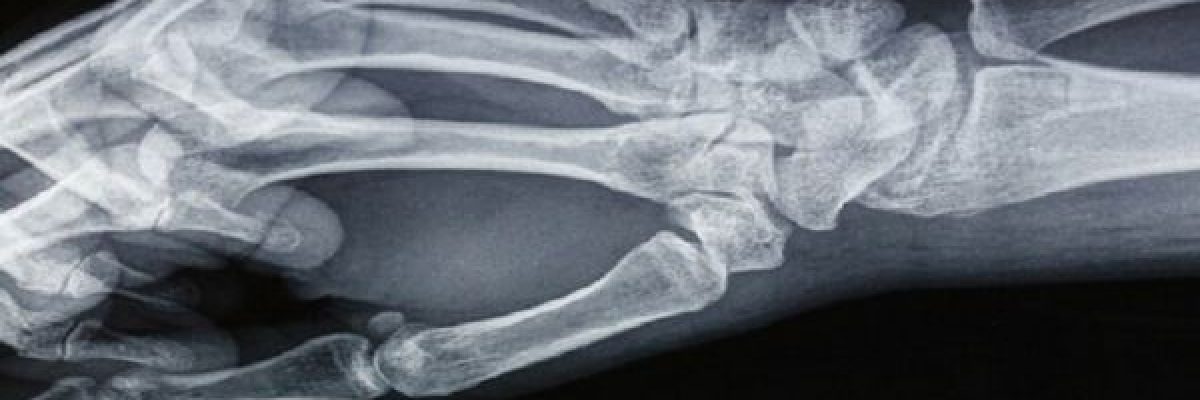

تعد حالات السقوط وكسور العظام احد اكثر الاصابات التي قد يواجهها الاشخاص في حياتهم اليومية، سواء اثناء السفر والتنزه او في المنازل ومقار العمل وغيرها.

3- تقسيم الاصابات الى كسور الاطراف العلوية، وكسور الاطراف السفلية، وكسور الحوض والعمود الفقري، والكسور المفتوحة والكسور المغلقة.